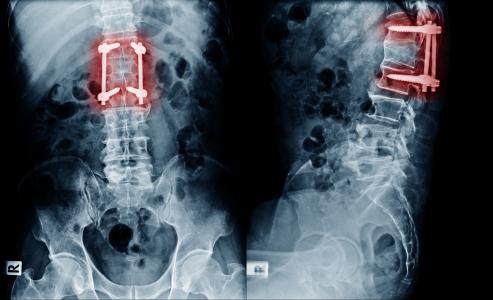

Des implants intelligents, auto-alimentés, développés par ces bioingénieurs de l’Université de Pittsburgh, permettent de surveiller la guérison de lésions de la colonne vertébrale, notamment en évaluant l’évolution de la fusion vertébrale ou fusion de 2 vertèbres. Alors que dans de nombreux cas, les chirurgiens utilisent une cage pour faire support là où le disque se trouvait autrefois entre les vertèbres, l’idée est d’utiliser une cage intelligente qui « participe » activement à la guérison. Cette cage est présentée dans la revue Advanced Functional Materials.

Une meilleure personnalisation : alors que les cages de fusion vertébrale utilisées dans les chirurgies de fusion vertébrale, sont généralement constituées de titane ou de matériaux polymères avec certaines propriétés mécaniques, la nouvelle cage intelligente, imprimée en 3D en fonction de l'anatomie et du besoin spécifique du patient, et avec un matériau réglable et évolutif, permet un ajustement beaucoup plus naturel.